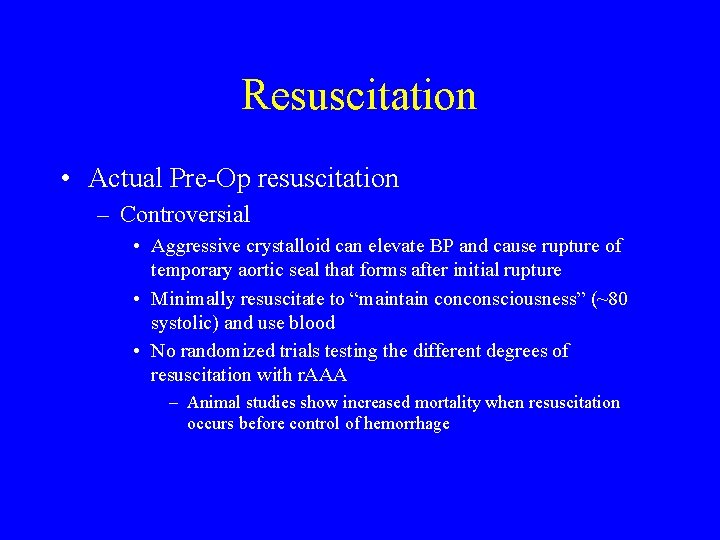

Resuscitation • Actual Pre-Op resuscitation – Controversial • Aggressive crystalloid can elevate BP and cause rupture of temporary aortic seal that forms after initial rupture • Minimally resuscitate to “maintain conconsciousness” (~80 systolic) and use blood • No randomized trials testing the different degrees of resuscitation with r. AAA – Animal studies show increased mortality when resuscitation occurs before control of hemorrhage